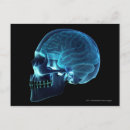

Röntgen från hjärnan inuti en skalle poster

Pris343,00 kr

Röntgen från hjärnan inuti en skalle canvastryck

Pris1 689,00 kr

Röntgen från hjärnan inuti en skalle vykort

Pris21,00 kr